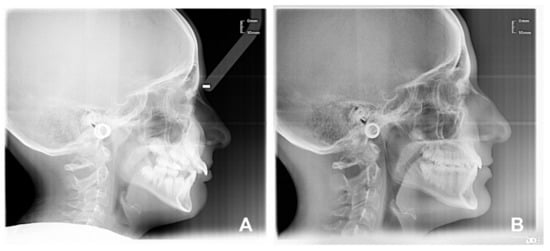

2.3. Treatment Protocol

- In very high-angle cases (S-N^-Go-Gn > 37°), first AMCOP® OPEN for 6–8 months and then the SC device;

- In slightly increased angle cases (32° < S-N^-Go-Gn ≤ 37°), first AMCOP® INTEGRAL for 6–8 months and then the SC device.